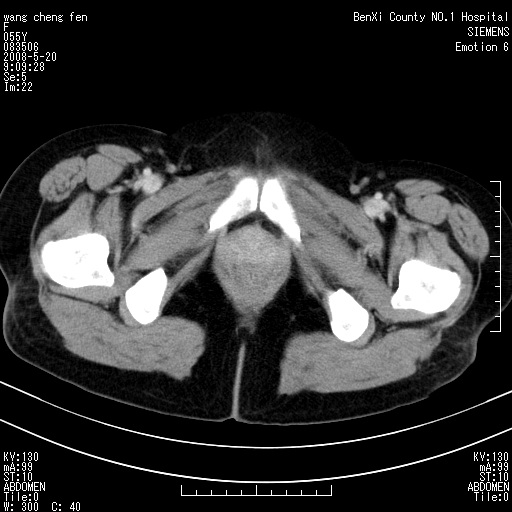

女、绝经后阴道流血3个月

左侧附件区可见一囊性占位,边缘清楚,内可见不规则形软组织影 ce:囊壁及内部可见强化 考虑 卵巢囊腺瘤

左侧附件区巨大囊实性病灶,边缘光整,病灶囊壁较厚,增强示囊壁及实性部分明显强化,强化呈度与宫体实质大致相同,宫腔积液征像,未见盆腔积液等其他异常,考虑左侧卵巢囊腺癌,不除外囊腺瘤及浆膜下肌瘤坏死

左侧附件区巨大囊实性病灶,边缘光整,病灶囊壁较厚,增强示囊壁及实性部分明显强化,强化呈度与宫体实质大致相同,宫腔积液征像,未见盆腔积液等其他异常。绝经后阴道流血3个月,结合病史左侧卵巢囊腺癌首先考虑,宫腔扩大不除外累及。期待结果。

支持浆膜下子宫肌瘤.之前由于网络原因未看全图片,现在重看,宫颈见一类圆形低密度影,增强轻度强化,低于肌层强化,宫腔扩大,考虑宫颈癌伴宫腔积液可能性大.